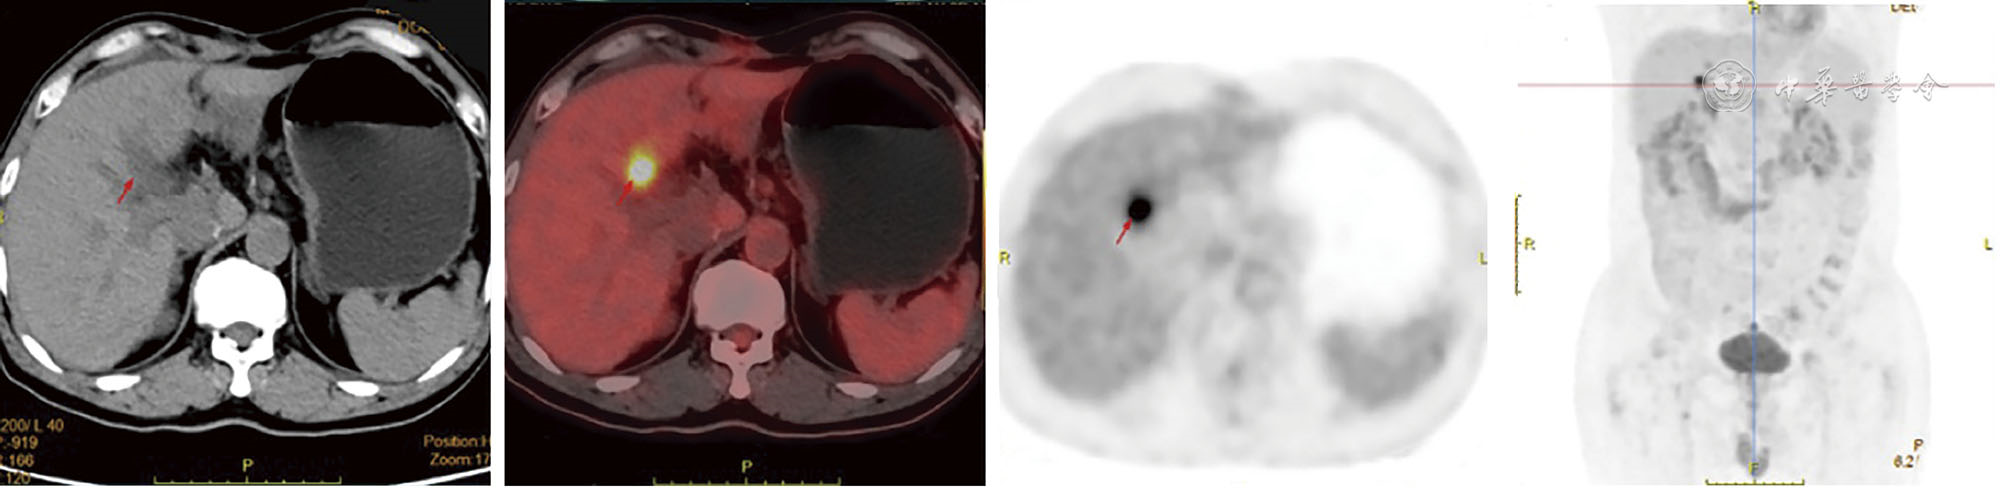

In this report, a 63-year-old male patient was admitted due to "dull pain in the right upper abdomen for 2 months". Imaging and pathological examination confirmed the diagnosis of synchronous hepatocellular carcinoma (CNLC Ⅰa stage) and duodenal papillary carcinoma (moderately-poorly differentiated adenocarcinoma complicated with signet ring cell carcinoma). The patient had a history of chronic hepatitis B. After Multidisciplinary team (MDT) consultation, laparoscopic local resection of segment 5 of the liver combined with pancreatoduodenectomy were performed to achieve R0 resection. Liver metastasis occurred 2 months after operation, and it was completely relieved after TACE, tirelizumab immunotherapy and FOLFOX4 chemotherapy. Postoperative survival time has exceeded 16 months. This case of synchronous double primary carcinoma of the liver and duodenal papilla is extremely rare, and it is likely to miss the diagnosis in clinical practice, suggesting that after the diagnosis of one type of malignant tumor, comprehensive evaluation is still needed to exclude other primary lesions. PET-CT shows important value in the early identification of such multiple primary cancers. Through multi-mode strategy of individualized comprehensive treatment and whole-course management, this patient achieved favorable tumor control effect, providing reference for clinical diagnosis and treatment of such rare cases.